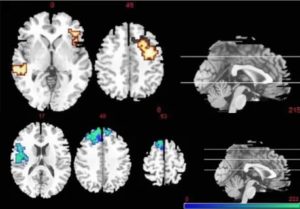

На данном снимке фМРТ (функциональное МРТ) приведено сравнение активности мозга в норме и пациента с шизофренией, у которого также выявлена трифуркация артерии.

Действительно специалисты в диагностике при исследовании больного с ранней шизофренией (рисунок ниже) выявляет повышение сигнала в лобной доле, а с поздней в височной доле (рисунок ниже).

Пациент с поздней шизофренией волнообразное течение. Выполнена фМРТ по данным которой повышенная активность в височной доле.

Больной с ранней шизофренией

МРТ — повышение активности лобной и затылочной доли.

Данный еще клинически здоровый молодой человек проходил обследование на МРТ

Обратился с головными болями. Многие отмечали, что он с изюменкой, но ничего плохого сказать о нем не могли. При классическом МРТ у данного пациента существенных изменений в головном мозге выявлено не было. При фМРТ патологическая активность в лобной доле -свидетельство ранней шизофрении.

Молодой человек не верил данному диагнозу спустя 8 лет обратился вновь, но уже с более грубой симптоматикой. На МРТ в классических протоколах были уже изменения в виде атрофии белого вещества головного мозга. Возможно данный пациент послужить плохим примером для пациентов, но ранняя лечение данному пациенту могло улучшить качество его жизни.